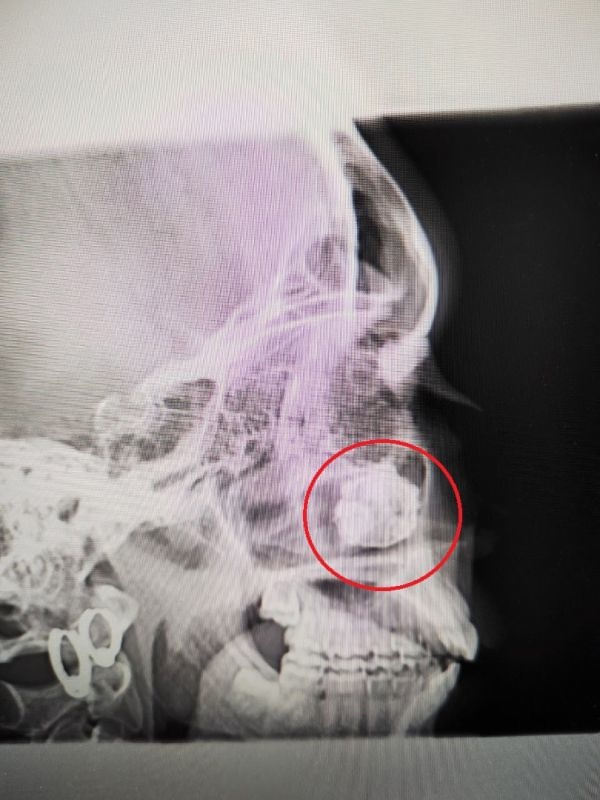

Ройс доставили в местную больницу вертолетом, а двум другим пострадавшим оказали медицинскую помощь на месте происшествия. Позже их госпитализировали для дальнейшего лечения. Им оказали медицинскую помощь и сделали вакцины от бешенства. Ройс наложили множество швов. Она также перенесла операцию на лице и ушах. В настоящее время пострадавшие восстановились и вернулись домой.